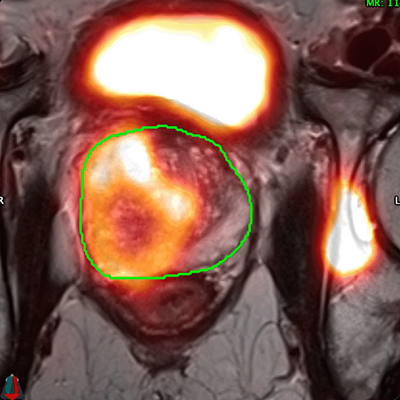

Before the procedure: Identify challenges and choose the optimal treatment modality using MR, PSMA PET Imaging, and 3D ablation energy

models.